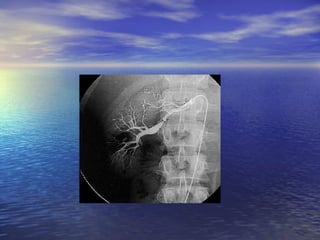

Hipertensión Vascular Renal En los jóvenes, en particular las mujeres, la  fibrodisplasia media   de   arteria renal  es la forma más común. En edad avanzada, son más comunes las lesiones por  aterosclerosis Diagnóstico definitivo:   Arteriografía renal.

Hipertensión Vascular RenalEn los jóvenes, en particular las mujeres, la fibrodisplasia media de arteria renal es la forma más común. En edad avanzada, son más comunes las lesiones por aterosclerosis Diagnóstico definitivo: Arteriografía renal.